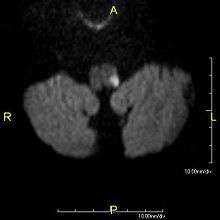

- MRI of Lateral Medullary Infarction (Wallenberg) MedPix Images